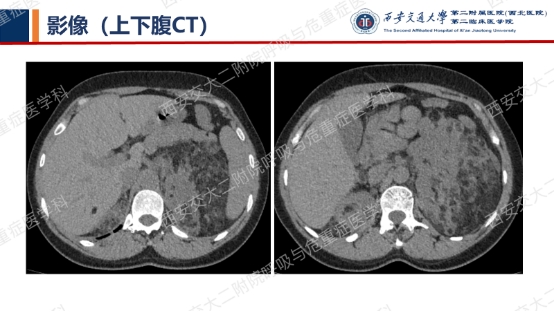

上图所示肺部多发囊性病变,双肺广泛分布,直径在2-10mm之间,壁薄,囊壁间组织相对正常。结合育龄期女性等临床资料,不难诊断淋巴管平滑肌瘤病(LAM)。对疑似LAM的女性的初步评估还应包括血管平滑肌脂肪瘤的筛查、淋巴管受累以及是否存在未被诊断的结节性硬化症。该例患者经评估后诊断散发型S-LAM。

上图与Case 2比较相似,所以诊断LAM没有问题,还需进一步排查系散发型还是结节性硬化症累及。

影像学评估发现患者多系统受累(肝脏错构瘤、双肾血管平滑肌脂肪瘤、颅脑多发异常信号结节)。追问病史,患者本人无皮疹、癫痫及智力低下;患者儿子有面部皮脂腺瘤,无癫痫及智力低下,胸腹部CT未见异常,皮肤科已确诊结节性硬化症;患者女儿面容及智力均正常;建议患者进一步行TSC基因检测,结果回报TSC2突变,结节性硬化症诊断明确。